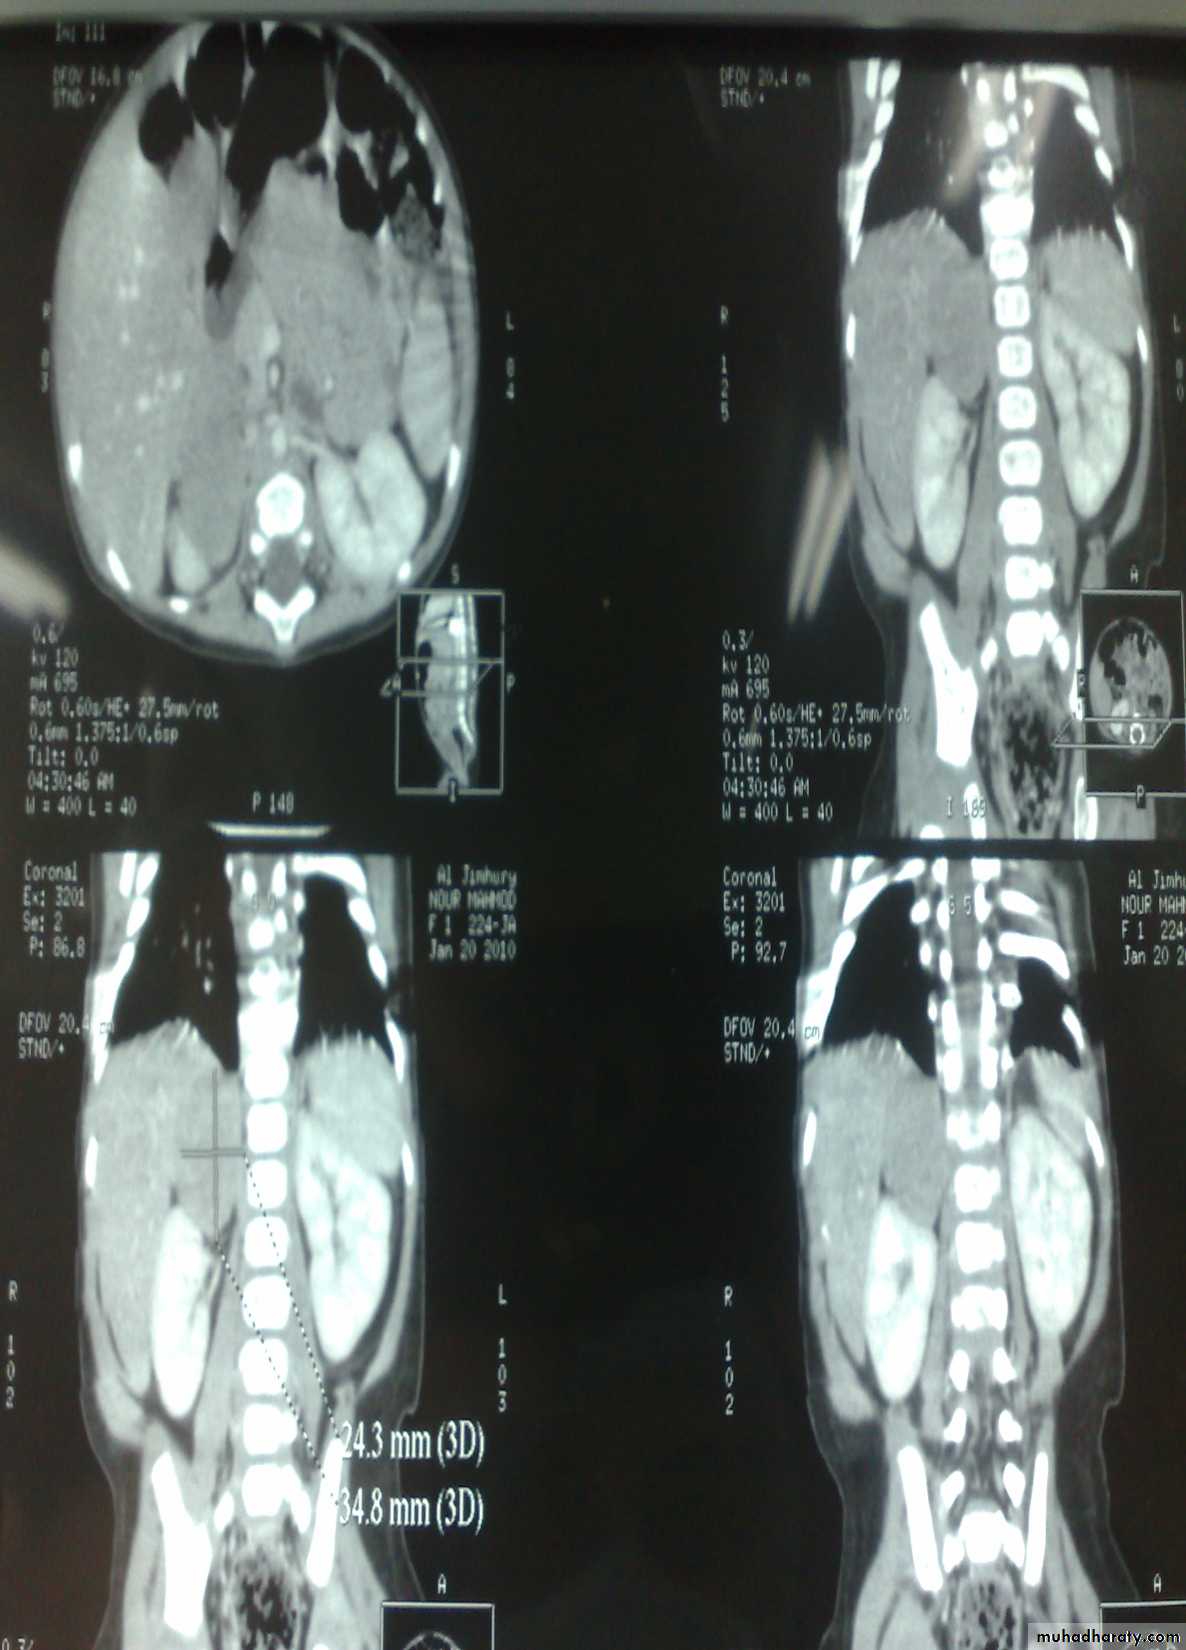

The Child with an Abdominal Mass5 years child, presented with mass in the flank.

DDx of mass in the flank:1- Wilms tumor

2- Neuroblastoma

3- Neglected PUJ obstruction

Presentation:

1- Mass2- hematuria

3- hypertension

Treatment by surgery remove the kidney + chemotherapy